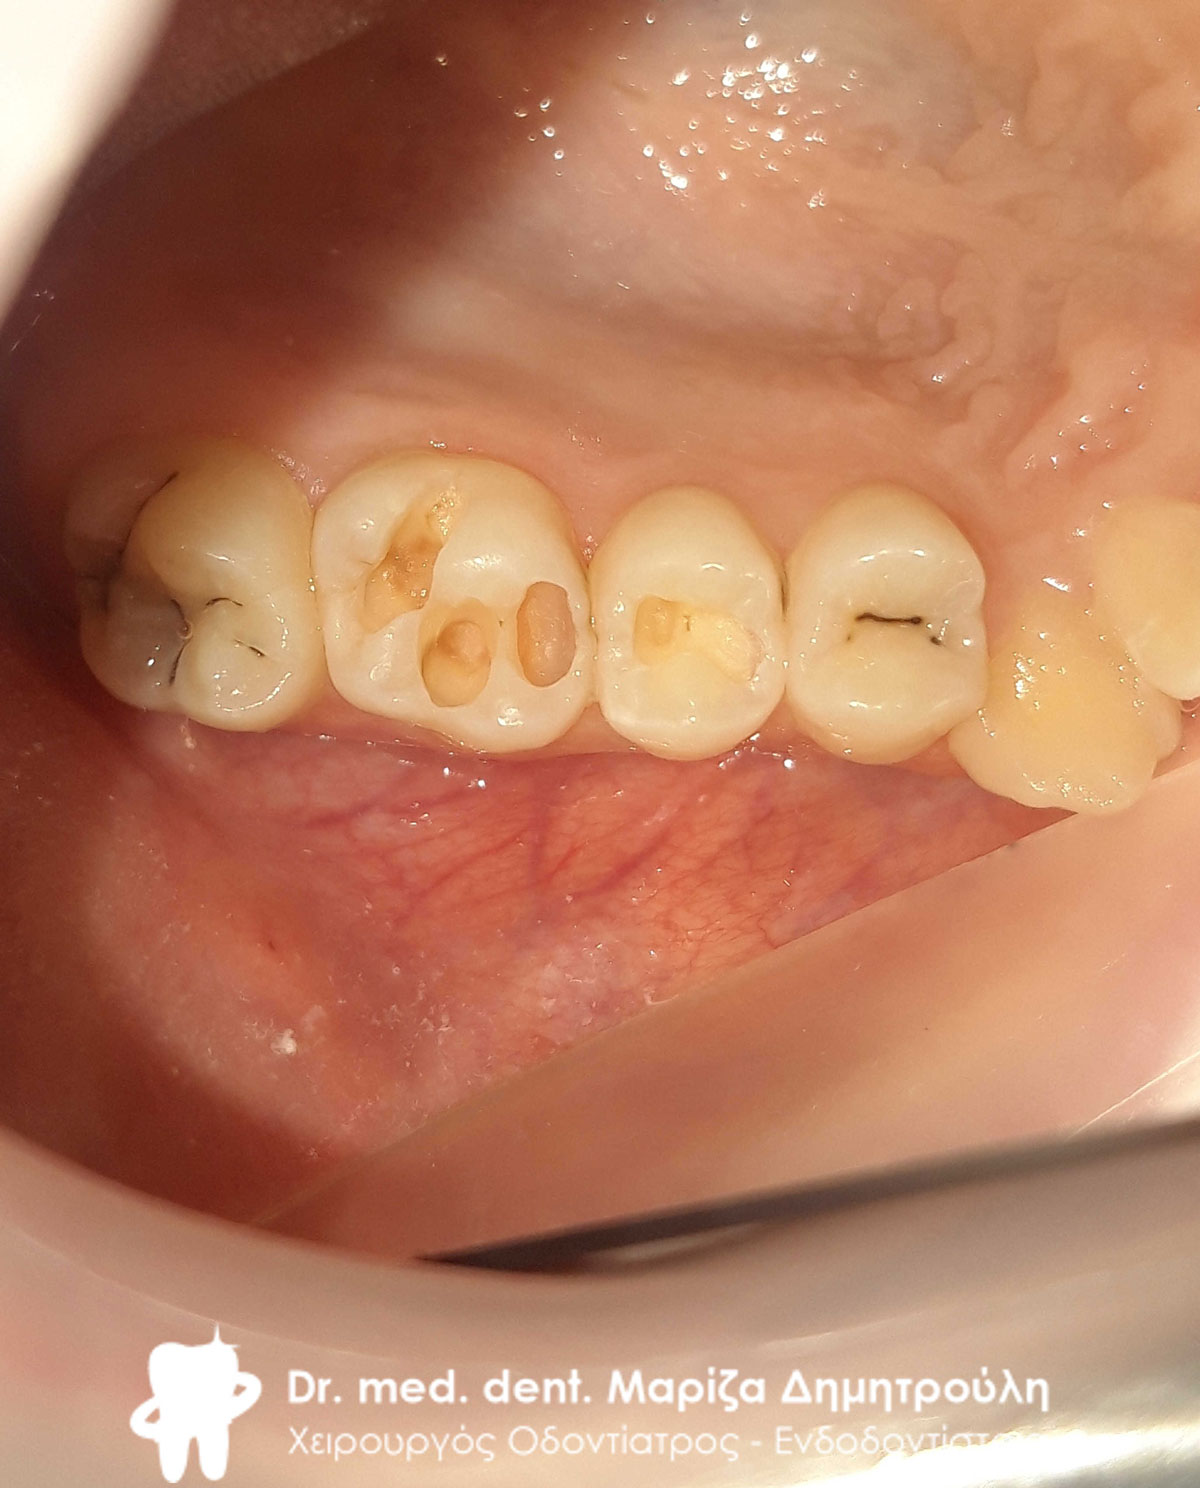

Αρχική κλινική εικόνα της δεξιάς πλευράς της άνω γνάθου